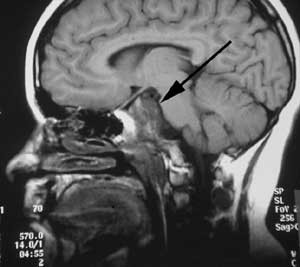

Pasient 1. Ni år gammel pike, født til termin, upåfallende psykomotorisk utvikling. Fra sju års alder klaget hun periodevis over svie/kløe i begge øynene og dobbeltsyn. Hun ble da bredt utredet uten resultat. Symptomene gikk delvis tilbake, men påfølgende år tilkom økende symptomer og man påviste da en bilateral abducensparese. Ny bildediagnostikk avslørte nå en stor ekspansiv prosess utgående fra clivus med affeksjon av pons, mest forenlig med et clivuskordom (fig 2a).

Det postoperative forløpet var meget tilfredsstillende. Hun kunne mobiliseres første dag etter inngrepet uten nye nevrologiske utfall. En postoperativ MR avslørte en liten resttumor (fig 2b). Hun ble derfor henvist og behandlet ved Stråleknivenheten, Nevrokirurgisk avdeling, Haukeland Universitetssykehus. Påfølgende år har hennes dobbeltsyn vært i jevn bedring. MR-kontroller har vist at resttumor er i regresjon.